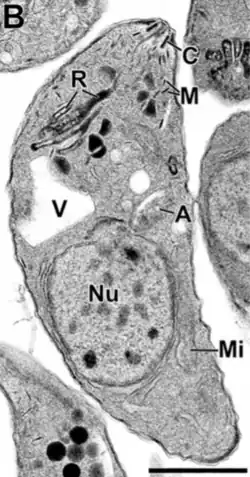

Algunos de los orgánulos que pueden ser encontrados en la imagen de microscopía electrónica de la derecha son:

apicoplasto (A); anillo polar apical (APR); conoide (C); anillo conoidal (CR); aparato de Golgi (G); complejo de membrana interna (IMC); Micronemas (M); mitocondria (Mi); microtúbulos (Mt); núcleo (Nu); roptrias (R); conducto de roptria (RD); vacuola (V).